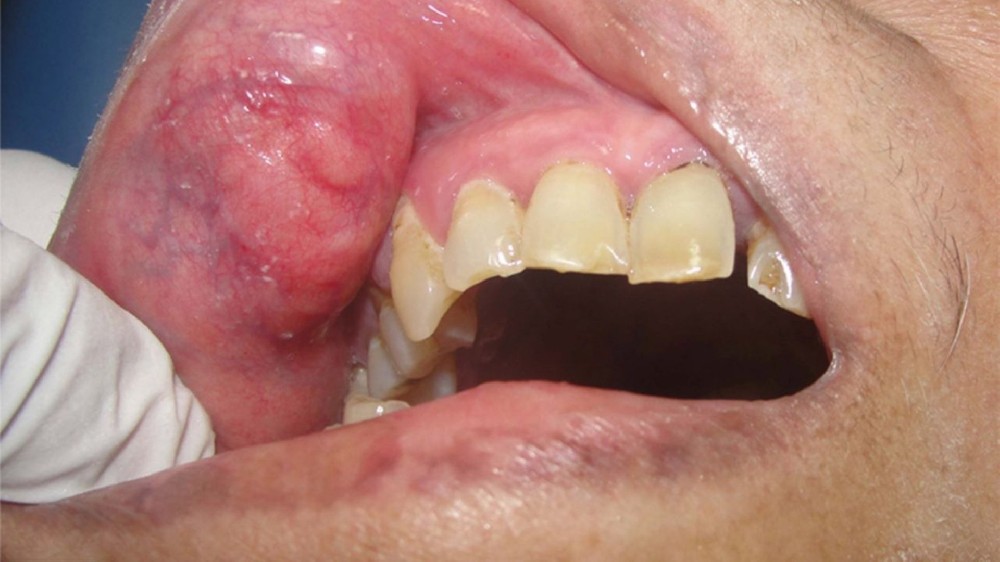

顎部、頸部或口腔周圍出現腫脹或腫塊

顎部、頸部或口腔附近出現腫塊或紅腫

早期唾液腺癌的症狀可能很輕微或沒有特異性,通常表現為無痛的腫脹或腫塊,常被誤診為感染或囊腫等良性疾病。早期識別雖具挑戰性,但可大幅改善預後。